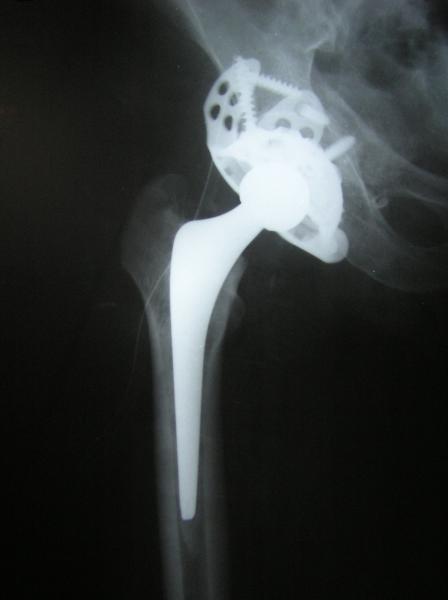

Surface Replacement of hip